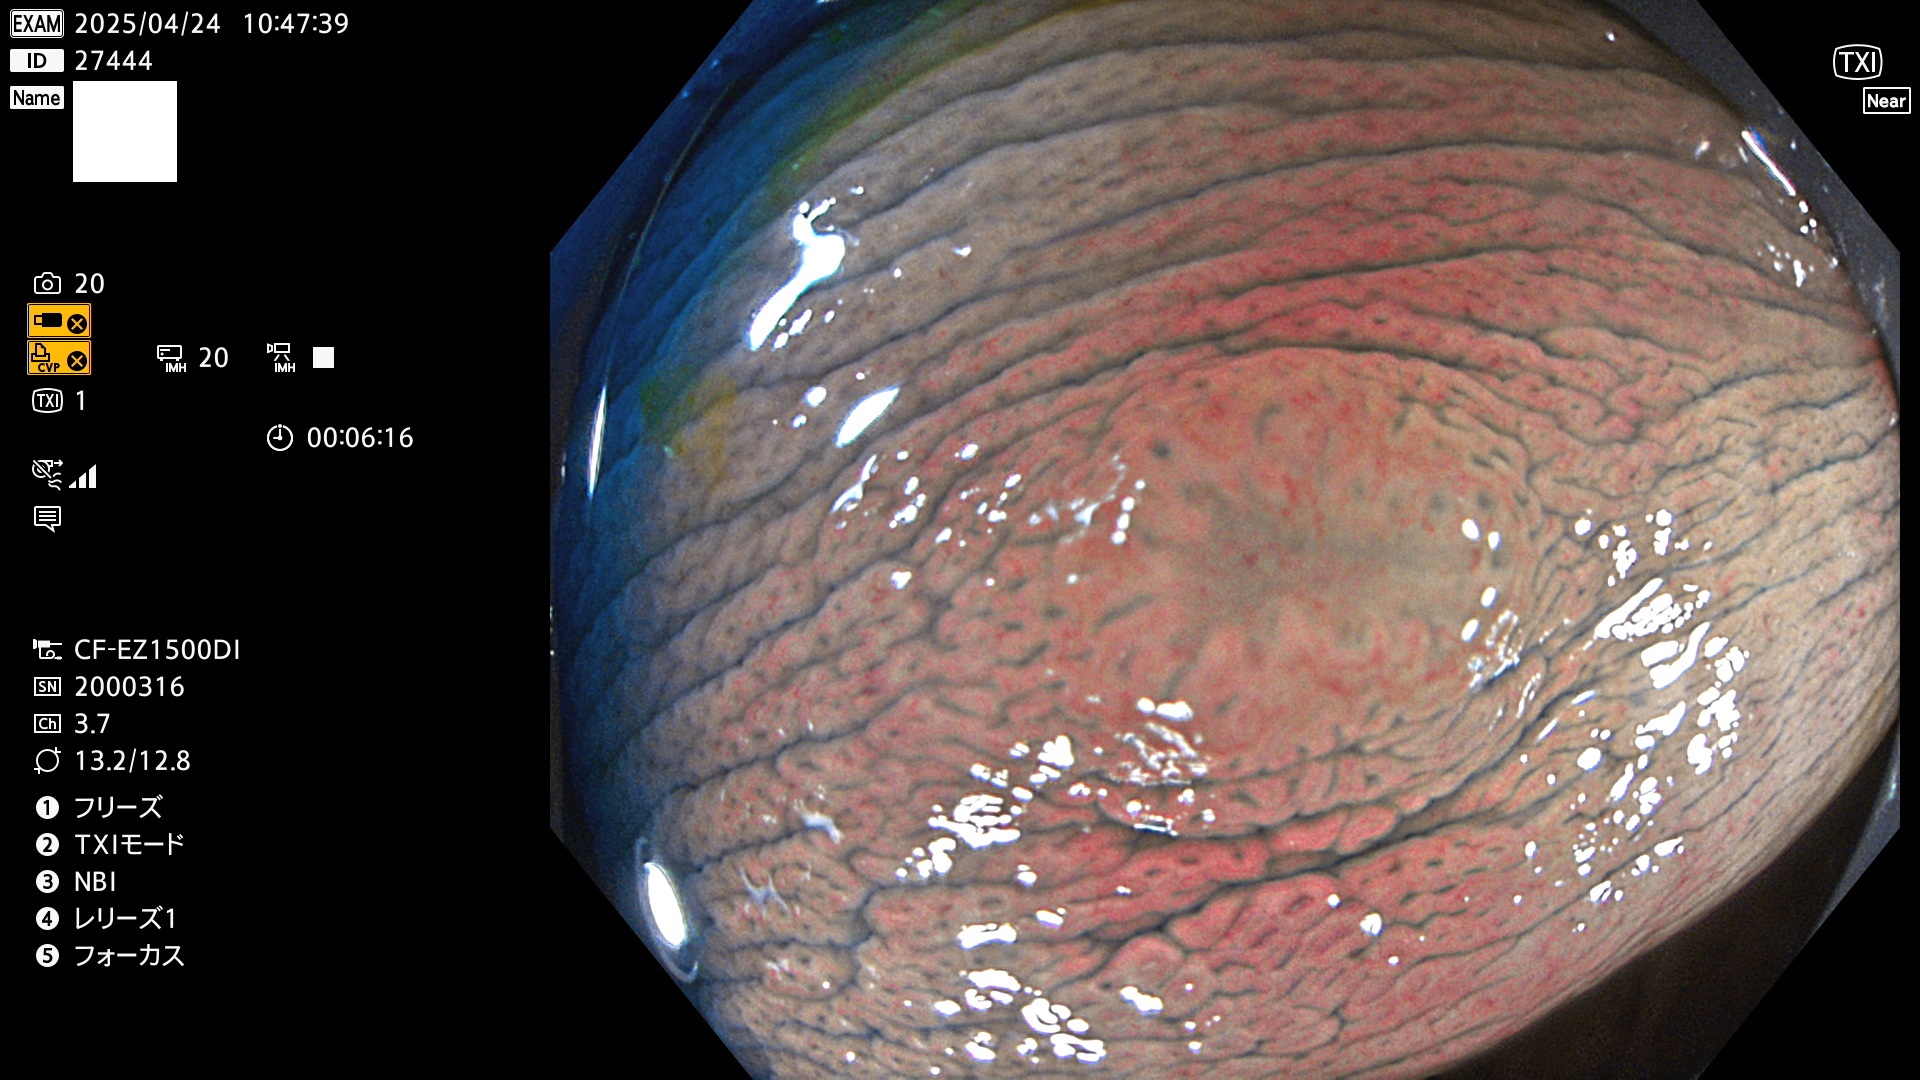

完全に平坦な物をUb、陥凹している物をUcと呼びます。Ubは認識が困難で、Ucはびらん(炎症)と紛らわしいために見落とされやすく、「内視鏡後・大腸癌」の原因になります。

抽出の対象期間 2025年4月24日〜4月27日の4日間(48件の検査)4個 (4/48=8%)